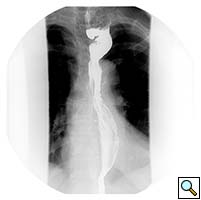

A 67 year old patient with a history of transhiatal esophagectomy (THE) and sub-sternal gastric pull-up ten years prior, at another institution, for early stage esophageal cancer presented with progressive dysphagia to solids. An initial esophagogastroduodenoscopy (EGD) found a large retained food bolus as well as tortuosity and dilatation of the cervical esophagus proximal to the esophagogastric anastomosis. No evidence of intrinsic anastomotic stricture or fibrosis was noted, but there was extrinsic compression. A barium esophagogram revealed significant extrinsic compression of the upper esophagus in the area of the anastomosis at the left clavicular head, with associated narrowing of the lumen and minimal transit of oral contrast (Figure 1). A computed tomography scan of the neck confirmed the sub-sternal location of the gastric pull-up within the anterior mediastinum, and revealed dilatation of the esophagus proximal to the anastomosis, with no associated masses or disease recurrence (Figure 2). The left sternoclavicular joint (SCJ) appeared to be compressing the conduit and was the point of obstruction.